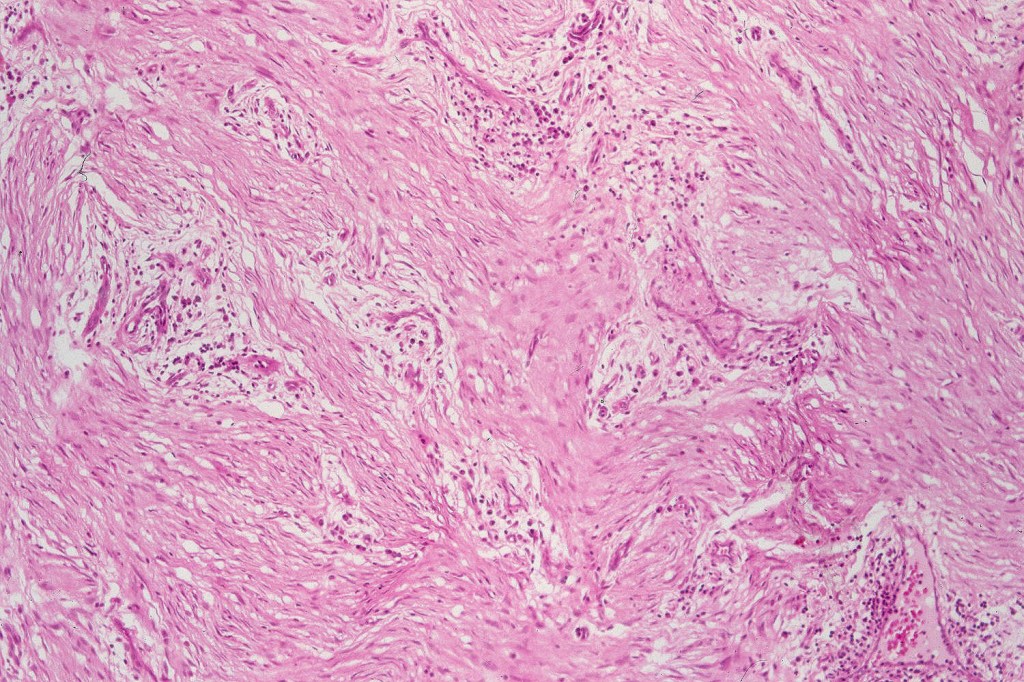

Cellular blue nevus

This uncommon most often devlops on the buttocks, sacrococcygeal region & distal extremities although it may be seen at just about any site. It shows a predilection for females and is diagnosed most often in the 2nd-4th decade. It presents as a blue-black/ or black nodule measuring 1-2 cm in dianeter. Similar to common blue nevus, the cellular variant can be encountered in a wide range of non-cutaneous locations.

Histological features

•Most characteristic is the dumbbell silhouette although a plague morphology may also be encountered

•Combined nevus variant

•Admixture of spindle cells, pigmented bipolar or dendritic cells & melanophages

•Cytoplasm is pale and nuclei are small with inconspicuous nucleoli

•An alveolar pattern is characteristic particularly with clear cell nodules

•Mitoses are typically very sparse or absent

•No atypical mitoses

•No Necrosis or lymphovascular invasion

•Multinucleate giant cells sometimes present

•Stromal fibrosis, myxoid change, vascular hyalinization with cyst formation are often seen

•Some tumors are composed spindle cells in a fascicular or neuronevoid pattern

•Perineural involvement may be seen

•Balloon cell change

•Desmoplastic variant

•Hypopigmented variant